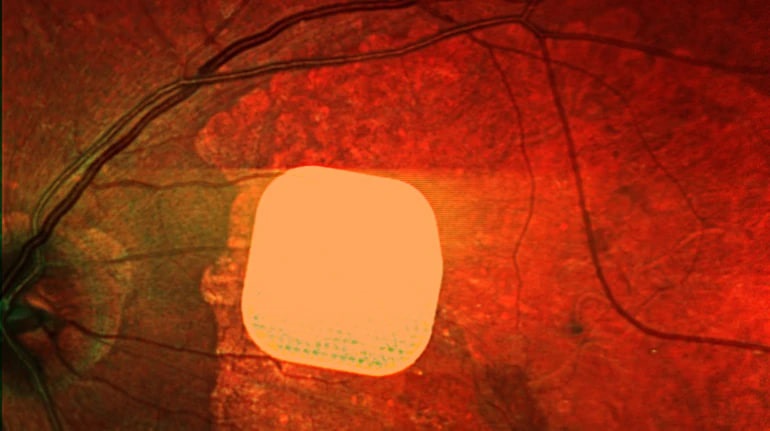

Британські лікарі успішно випробували новий електронний імплант Prima, який допомагає частково відновити зір пацієнтам із макулодистрофією – головною причиною втрати зору після 50 років. Цей мікрочип розміром лише 2×2 міліметри встановлюють під сітківку ока пацієнта під час операції, під’єднуючи його до системи окулярів доповненої реальності. Після операції 84% учасників дослідження знову змогли розрізняти літери, цифри та слова. Лікарі вважають, що ця технологія відкриває нові можливості для людей з важкими зоровими порушеннями, дозволяючи покращити їхню якість життя.